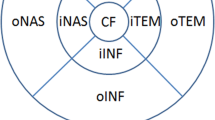

Posterior segment exploration was carried out after the initial screening of all participants after a break and wash-out period. The same trained examiner (Neus Burguera-Giménez) performed the choroidal analysis between 3:00 and 7:00 PM to limit the confounding effects of diurnal variations of CT [21]. Choroidal images were obtained using the DRI-1 Swept-Source (Topcon Medical, Tokyo, Japan), which presents the following specifications: a 1050-nm wavelength light source, a scanning speed of 100,000 A scans/s, an angle picture of 43°, and an in-depth and lateral resolution of 5 and 20 μm, respectively. Two pattern scans, both centered on the fovea, were used: one single-line and 12 radial-line B-scans. The OCT image of 12 mm provided by the single-line scan was used to determine the SCT by two masked observers (Neus Burguera-Giménez, María Amparo Díez-Ajenjo). SCT was manually quantified just under the fovea as the perpendicular distance between the outer boundary of the retinal pigment epithelium (RPE) and the inner boundary of the choroid-sclera junction (Fig. 1A). The OCT image of the 12 radial-line B-scans was used for the quantitative analysis of CT values and CT topography in the nine subfields based on the ETDRS grid.

Scan patterns selected to analyze choroidal thickness (CT). A B-scan obtained from one single-line scan, where, subfoveal choroidal thickness (SCT) was manually measured as the axial distance between the retinal pigment epithelium (RPE) (dashed red line) and choroidal-scleral junction (dashed blue line). B Choroidal thickness (CT) map obtained from 12-mm radial B-scan, where CT was automatically provided in the central ring (1 mm in diameter), central CT (cCT), and in different macular sectors based on the Early Treatment Diabetic Retinopathy Study (ETDRS) style grid. The inner ring (3 mm in diameter) which includes the nasal inner macula (iNAS), superior inner macula (iSUP), temporal inner macula (iTEM), and inferior inner macula (iINF). The outer ring involves the nasal outer macula (oNAS), superior outer macula (oSUP), temporal outer macula (oTEM) and inferior outer macula (oINF)

A three-dimensional topographic map was automatically generated, which provided CT in nine subfields defined by the ETDRS style-grid (Fig. 1B). The subfoveal macula (1-mm central ring, cCT), inner ring (3 mm in diameter) which includes the nasal inner macula (iNAS), superior inner macula (iSUP), temporal inner macula (iTEM), and inferior inner macula (iINF). The outer ring includes the nasal outer macula (oNAS), superior outer macula (oSUP), temporal outer macula (oTEM) and inferior outer macula (oINF). The device has an automatic layer segmentation that identifies choroidal boundaries for each 12-mm radial scan. Then, using the built-in segmentation-modifying tool, each line was inspected individually by the two observers to verify both boundaries and if both agreed on the need for manual correction, the original segmentations were modified. Swept-source optical coherence tomography (SS-OCT) provided a choroidal index quality (CIQ) to evaluate the quality of the choroidal images. Hence, only scans with a CIQ score of ≥ 60 were included in the current study.